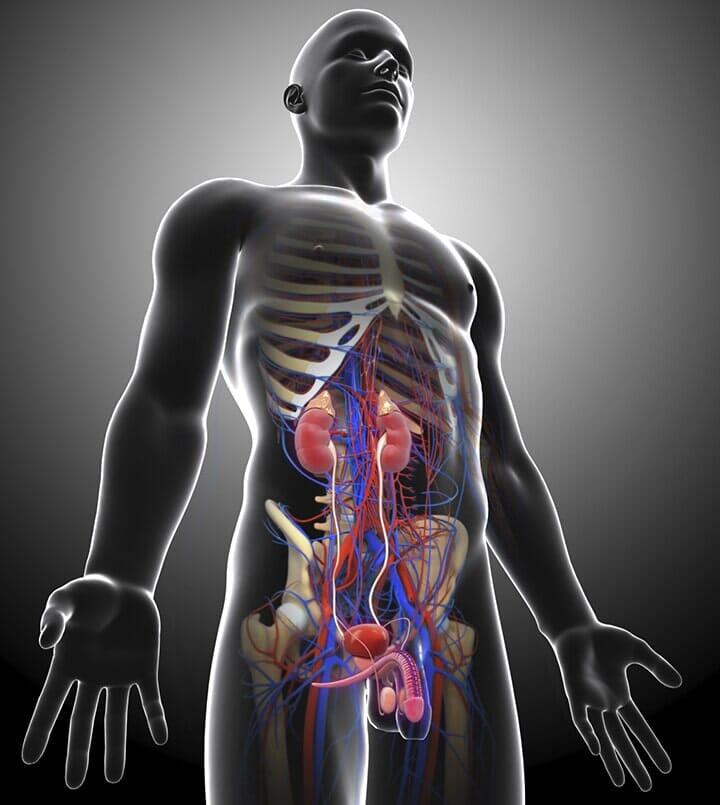

¿Sientes dolor en el riñón? Deja de sufrir de dolores intensos, el Dr. José Jorge Santibáñez Flores es un médico urólogo con consultorio en Celaya, Guanajuato, quien suma más de 10 años de experiencia en el sector de la salud.

Dr. José Jorge Santibáñez Flores, quien cuenta con una alta especialidad en cirugía láser y laparoscopia.

Conoce más sobre los servicios médicos que proporciona

Cirugías: